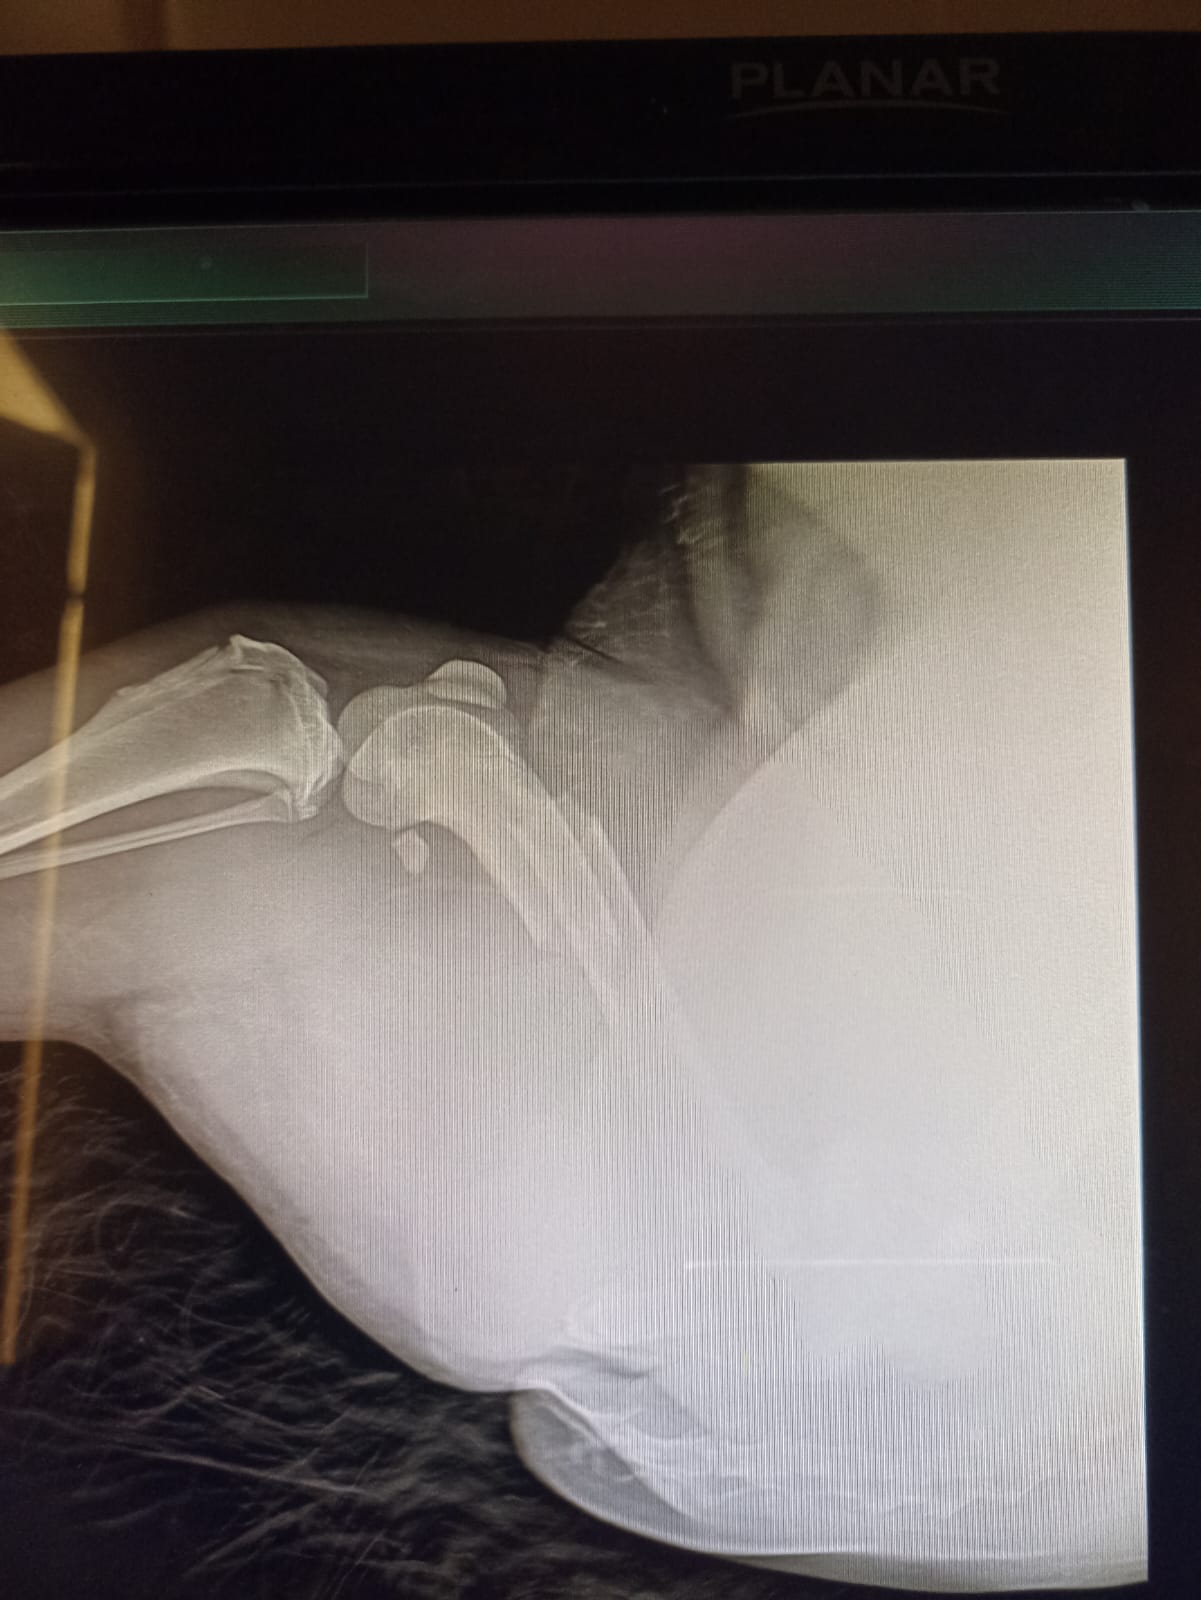

Волонтёр привела молодую суку ризена со сломанной лапой в клинику к Насте pani Stasi. Вроде перелом не сильно свежий.

Ногу будет хирург смотреть и может в ближайшее время прооперируют.

Её забрала заводчица. И что-то там у них случилось, то ли лошадь понесла, то ли что, в общем, собака перепрыгивала через телегу и сломала лапу. У заводчицы тоже ключица сломана, может ещё что-то.

Ветеринар позвонила знакомому волонтёру, говорит, чего усыплять, я её соберу, рентген только надо.

Операцию сделали, собрали лапу на две пластины. Выписка попозже будет.

Да, задняя правая сломана.